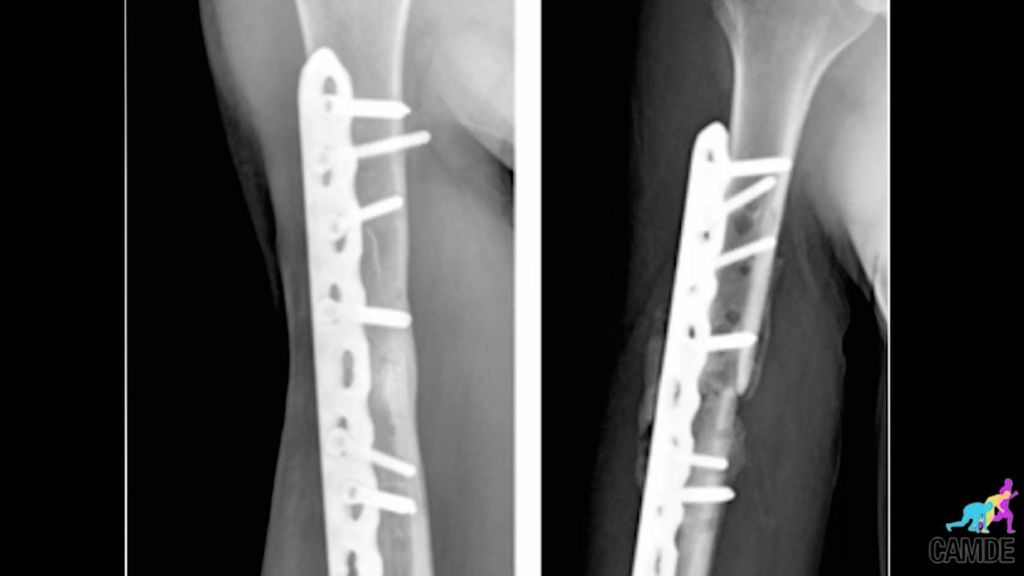

Cuando todo parecía correcto, empezó un calvario brutal que Marc Márquez nunca olvidará. Todo comenzó cuando una caída en la primera carrera del Mundial de 2020 provocó que se rompiera el húmero. El 21 de julio de 2020 fue operado de esa fractura del tercio medio del húmero de su brazo derecho. Poco después, a principios de agosto, Márquez se tuvo que operar de nuevo del mismo húmero derecho debido a "un mal gesto doméstico en su casa, abriendo una ventana". Ahí se vio que la placa de titanio para fijar la fractura que le habían puesto se había roto. Se llegó insinuar que el hecho de querer correr en Jerez tras la operación fue la causante.

Marc Márquez arrastró la lesión en el humero derecho hasta mediados de 2021. Ya parecía que todo volvía a su curso, pero no fue así. Las molestias no se iban a pesar de que ya le habían quitado la placa de titanio. En diciembre pasó por tercera vez por el quirófano. Un hecho que le supuso cierta mejora y le permitió competir en algunas carreras de la temporada de 2022, pero entre la famosa diplopía y que la cosa no terminaba de ir bien, a principios de junio se operó por cuarta y última vez del hombro derecho. La cicatriz que le ha quedado es cuando menos impactante... [video_mediaset id="30178"]